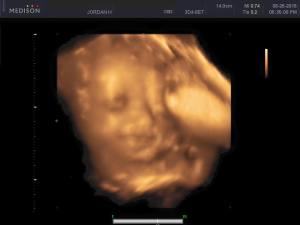

Baby Facts: We had our 3D/4D ultrasound this week. IT WAS AMAZING! Worth every penny. We confirmed baby is in no doubt A GIRL! (Good thing too…I didn’t want to return all the pink). We also got to see her adorable little face, which made me tear up a little bit. It amazes me how the body turns something so tiny into a little human in just 40 weeks.

Anyways, baby has some chubby cheeks already, as you can see. She also is already facing the correct way for her arrival into the world. The funniest moment is seeing how tight she is getting in there, our little goof was getting a bit too close to my belly and ended up squashing her nose a couple of times. (lol)